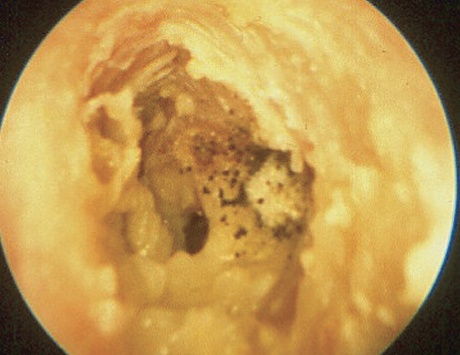

| Bệnh nhân bị viêm tai ngoài do nấm. Ảnh: N.P. |